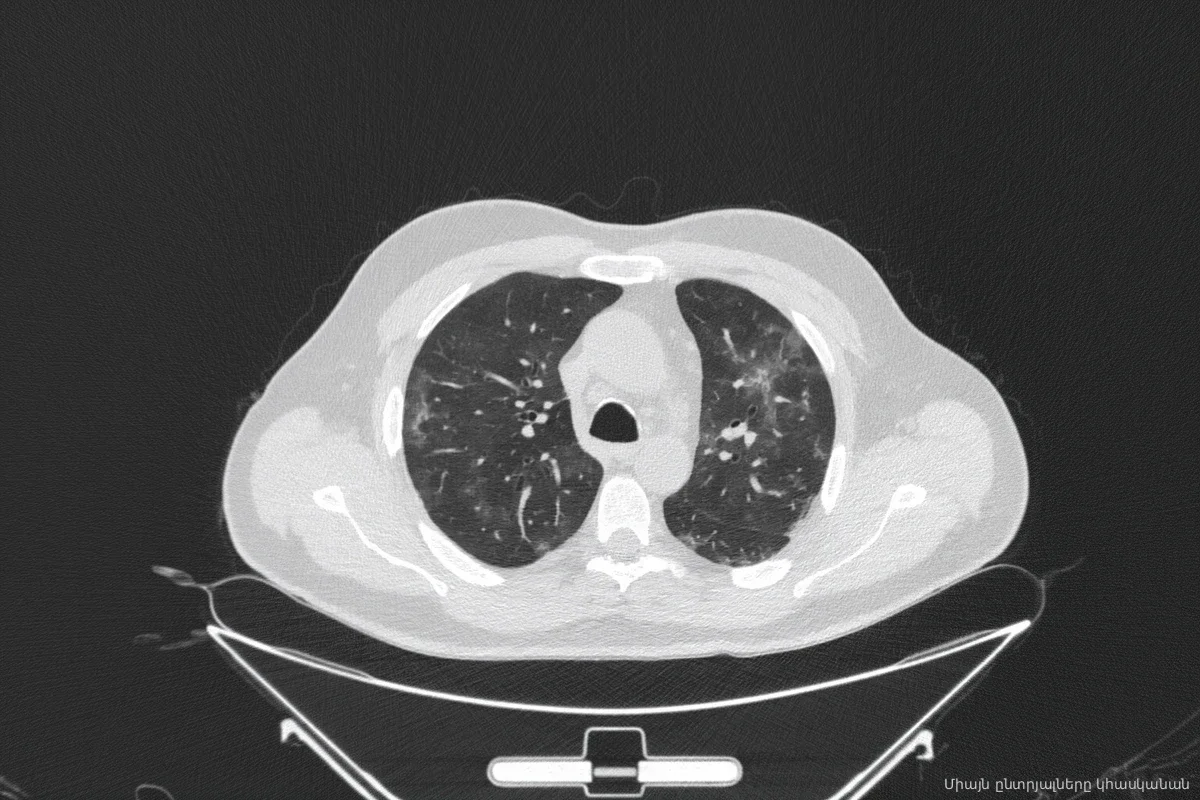

Новосибирская область переходит на новую систему раннего выявления рака легких. Региональный Минздрав утвердил порядок обязательного обследования пациентов из групп риска с помощью низкодозной компьютерной томографии (НДКТ). Ставка сделана на точечную диагностику: медики намерены находить опухоли до того, как они станут смертельно опасными.

Под прицелом врачей оказались жители региона в возрасте от 50 до 75 лет со стажем курения 30 лет и более, а также те, кто расстался с вредной привычкой менее 15 лет назад. Теперь медики обязаны выявлять таких пациентов не только в ходе плановой диспансеризации, но и при любом обращении в поликлинику. Данные о «курительном стаже» и степени риска сразу фиксируются в единой цифровой системе региона. При этом лишних обследований не будет: если пациент уже проходил НДКТ в последние 11 месяцев, повторную процедуру не назначат. Если же диагностика подтвердит подозрение на опухоль, у клиники есть всего три рабочих дня, чтобы направить человека в центр амбулаторной онкологической помощи и закрепить за ним точную дату приема.

Статистика неумолима: типичному пациенту с раком легкого в области от 65 до 69 лет. Это заболевание прочно удерживает четвертое место в региональной структуре онкологии (8,6%). Ситуация с ранним выявлением остается непростой: на начальных стадиях болезнь находят лишь в четверти случаев, в то время как почти 30% диагнозов ставится уже на запущенной, третьей стадии. Помимо табачного дыма, на здоровье жителей влияют специфические региональные факторы: высокая концентрация радона, неблагоприятная экология и тяжелые условия труда на производствах.